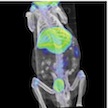

MicroPET/CT, MicroSPECT/CT, MicroCT, and Optical Imaging

We offer nuclear, x-ray, and optical imaging solutions utilizing dual-modality microPET/CT and microSPECT/CT, and bioluminescence/fluoresence imaging systems. Our housing facility is managed by LARC and is classified as an “in-and-out” facility that is well suited for longitudinal studies. Our imaging scanners are run by highly trained professionals. We also have imaging science experts to provide additional help on image reconstruction, co-registration, tracer kinetic modeling, and quantifications.